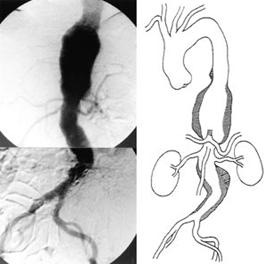

- Angiography aorta (aortography) (gb. 16)—diindikasikan sebelum repair aneurisma arterial oclusive disease pada viseral dan ekstremitas bawah atau saat repair endograft akan dilakukan.

clip_image025 clip_image027

Gambar 16: Aortography aorta abdominalis pada aneurisma aorta